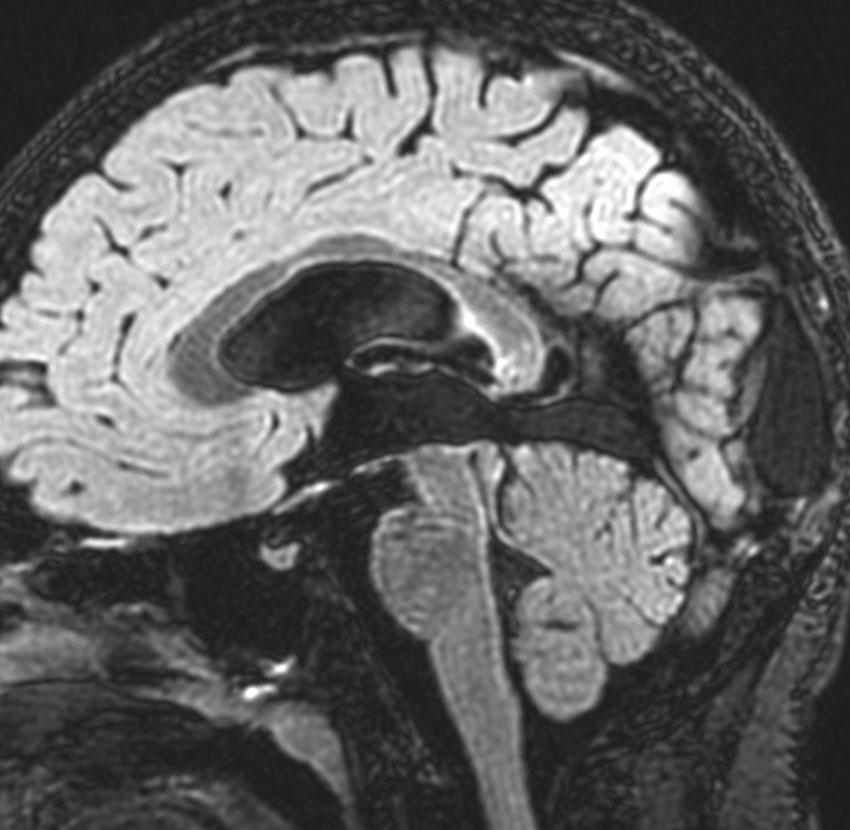

9歳男児の松果体奇形腫です。生検術と第3脳室開窓術を受けましたが,摘出術のリスクが高すぎるということで化学療法を6コース。2年間経過観察されましたが,腫瘍が増大しました。私のところへ来た時には,前後径73mmありました。

左からT2, swan, T1です。これが 類皮のう胞 dermoid cyst ということがわかります。類皮のう胞単独,あるいは成熟奇形腫の大部分としての類表皮のう胞は,かなり頻度の高いものです。松果体腫瘍で奇形腫を疑ったらまず,類皮のう胞の混在を疑います。それがあれば,かなりの確率で成熟奇形腫 mature teratomaです。

類皮のう胞は内部がほとんど皮脂,ケラチン,汗,毛髪なので,簡単に砕けるし,掻き出し吸い取ることができます。松果体成熟奇形腫の中では最も戦いやすい相手と言えるでしょう。再発しないようにするには,周囲ののう胞壁(真の腫瘍細胞)を完全摘出するしかありません。放射線も化学療法も何も効かないし,のこせば必ず再発します。

右迂回槽にちょっとdebrisは残っていますが完全摘出できました。病理は他の成分を少し混じる成熟奇形腫です。術後3年間再発はありませんし,学校へ通って体育もできています。

この手術はもちろん簡単ではありません,でもほとんどが類皮のう胞であるということがわかったので踏み込めたのです。